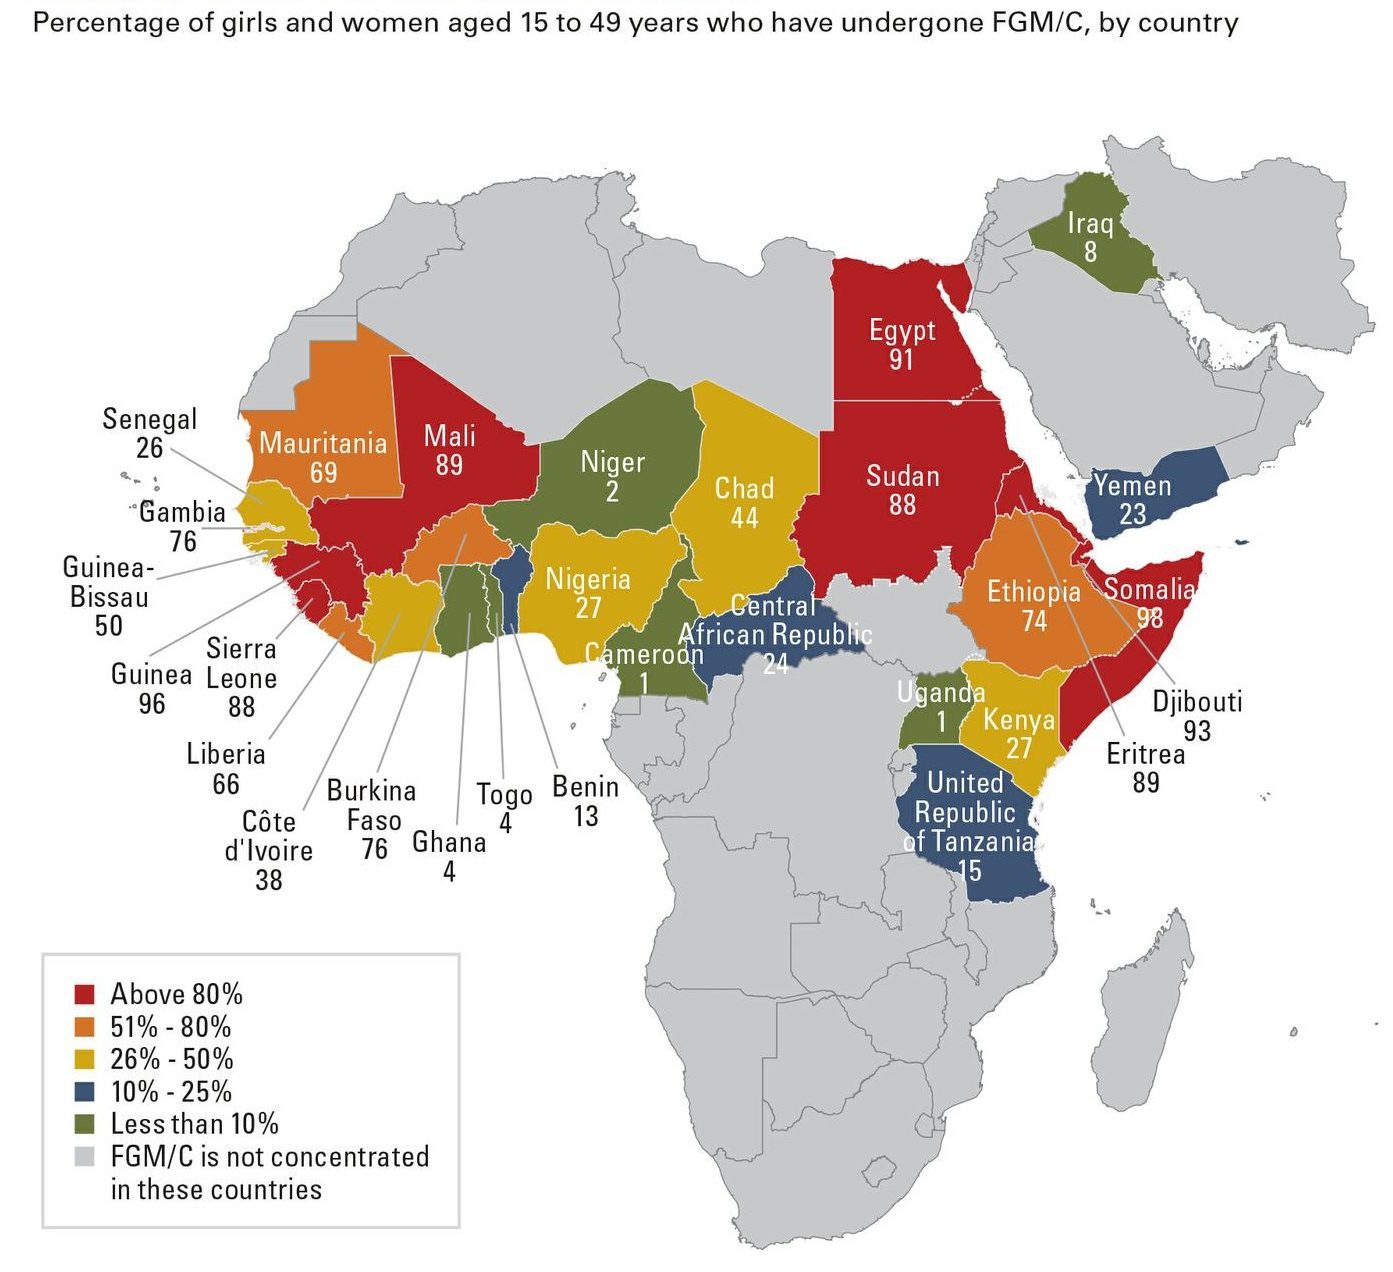

वर्ल्ड हेल्थ आर्गेनाइजेशन द्वारा फरवरी 2017 में एक फैक्ट रिपोर्ट जारी की गयी है जिसके तथ्य ना सिर्फ चौंकाने वाले हैं, बल्कि महिलाओं की जिंदगी की एक ऐसी सच्चाई से रूबरू कराते हैं, जो रूह कंपा देने वाली है| WHO के अनुसार विश्व जनसंख्या में 20 करोड़ महिलाएं ऐसी हैं जो अमानवीय व्यवहार का शिकार होती हैं और वह भी बिना वजह. इन 20 करोड़ महिलाओं के जननांग के बाहरी हिस्से को पूरी तरह काट कर निकाल दिया है, जो अमानवीय तो है ही काफी पीड़ादायक भी है | इस प्रक्रिया को Female genital mutilation (FGM या महिलाओं का खतना) कहा जाता है. यह परंपरा अफ्रीका, मध्य पूर्व और एशिया में कायम है. भारत में भी यह परंपरा व्याप्त है | भारत के आन्ध्र प्रदेश, बंगाल और बिहार समेत कई मुस्लिम बहुल स्थानों पर यह कुरीति व्याप्त है |

महिलाओं का खतना यानि FGM (Female genital mutilation) एक ऐसी प्रक्रिया है जिसमें महिलाओं और लड़कियों के योनी के भगोष्ठ को गैर-चिकित्सा कारणों से काटकर निकाल दिया जाता है| इस प्रक्रिया का कोई शारीरिक फायदा महिलाओं को नहीं होता है| इस प्रक्रिया में अत्यधिक रक्तस्राव होता है और इसके बाद महिलाओं में पेशाब की समस्या उत्पन्न हो जाती है. साथ ही कई तरह के संक्रमण और प्रसव के दौरान जटिलताएं भी उभर आती हैं, जिसके कारण कई बार नवजात की मौत भी हो जाती है. जब लड़की छोटी होती है तभी उसके साथ इस तरह की क्रिया को अंजाम दिया जाता है|